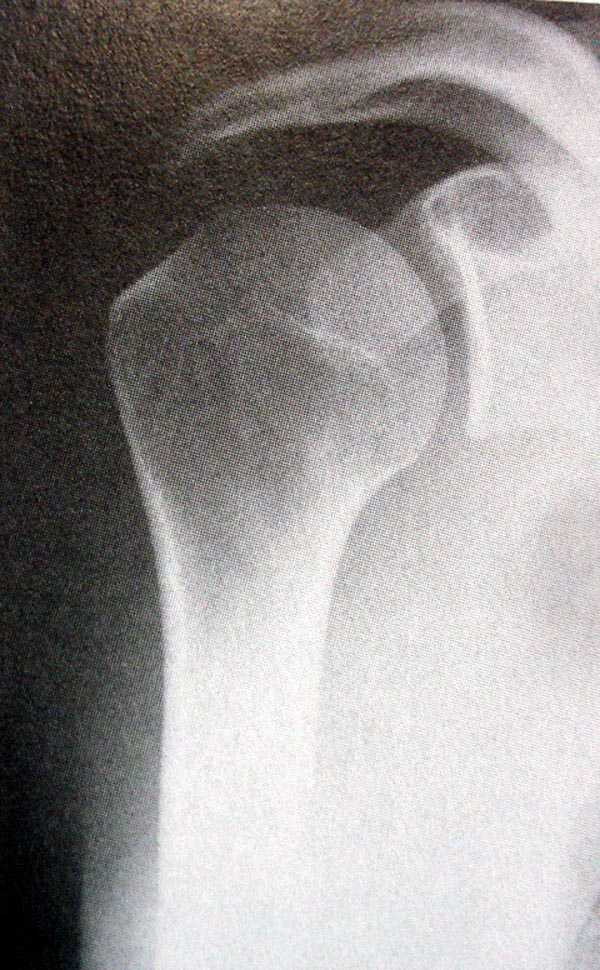

Re: Закрытый оскольчатый перелом хир. шейки плеча со смещением

Рентгенологические исследования проксимального отдела плеча состоит из прямого, бокового и аксиальных видов. Если имеются сложные переломы тогда рекомендуется Томография, а так в большинстве случаев достаточно бывает стандартных снимков.

Независимо от условий (нежелание рентгентехника или отсутствие пленок) необходимо добиться рентгенограмм, особенно аксиальной, потому что одна проекция не гарантирует, что не пропущен вывих в плечевом суставе.

На выставленных снимках копии из книги: 1-2 прямая укладка и снимок; 3-3a боковой или Y; 4 аксиальная укладка и снимок.

Для принятия решения и исследования обычно достаточно пару дней, а здесь третья неделя, начало консолидации метафизарной части, надо спешить!